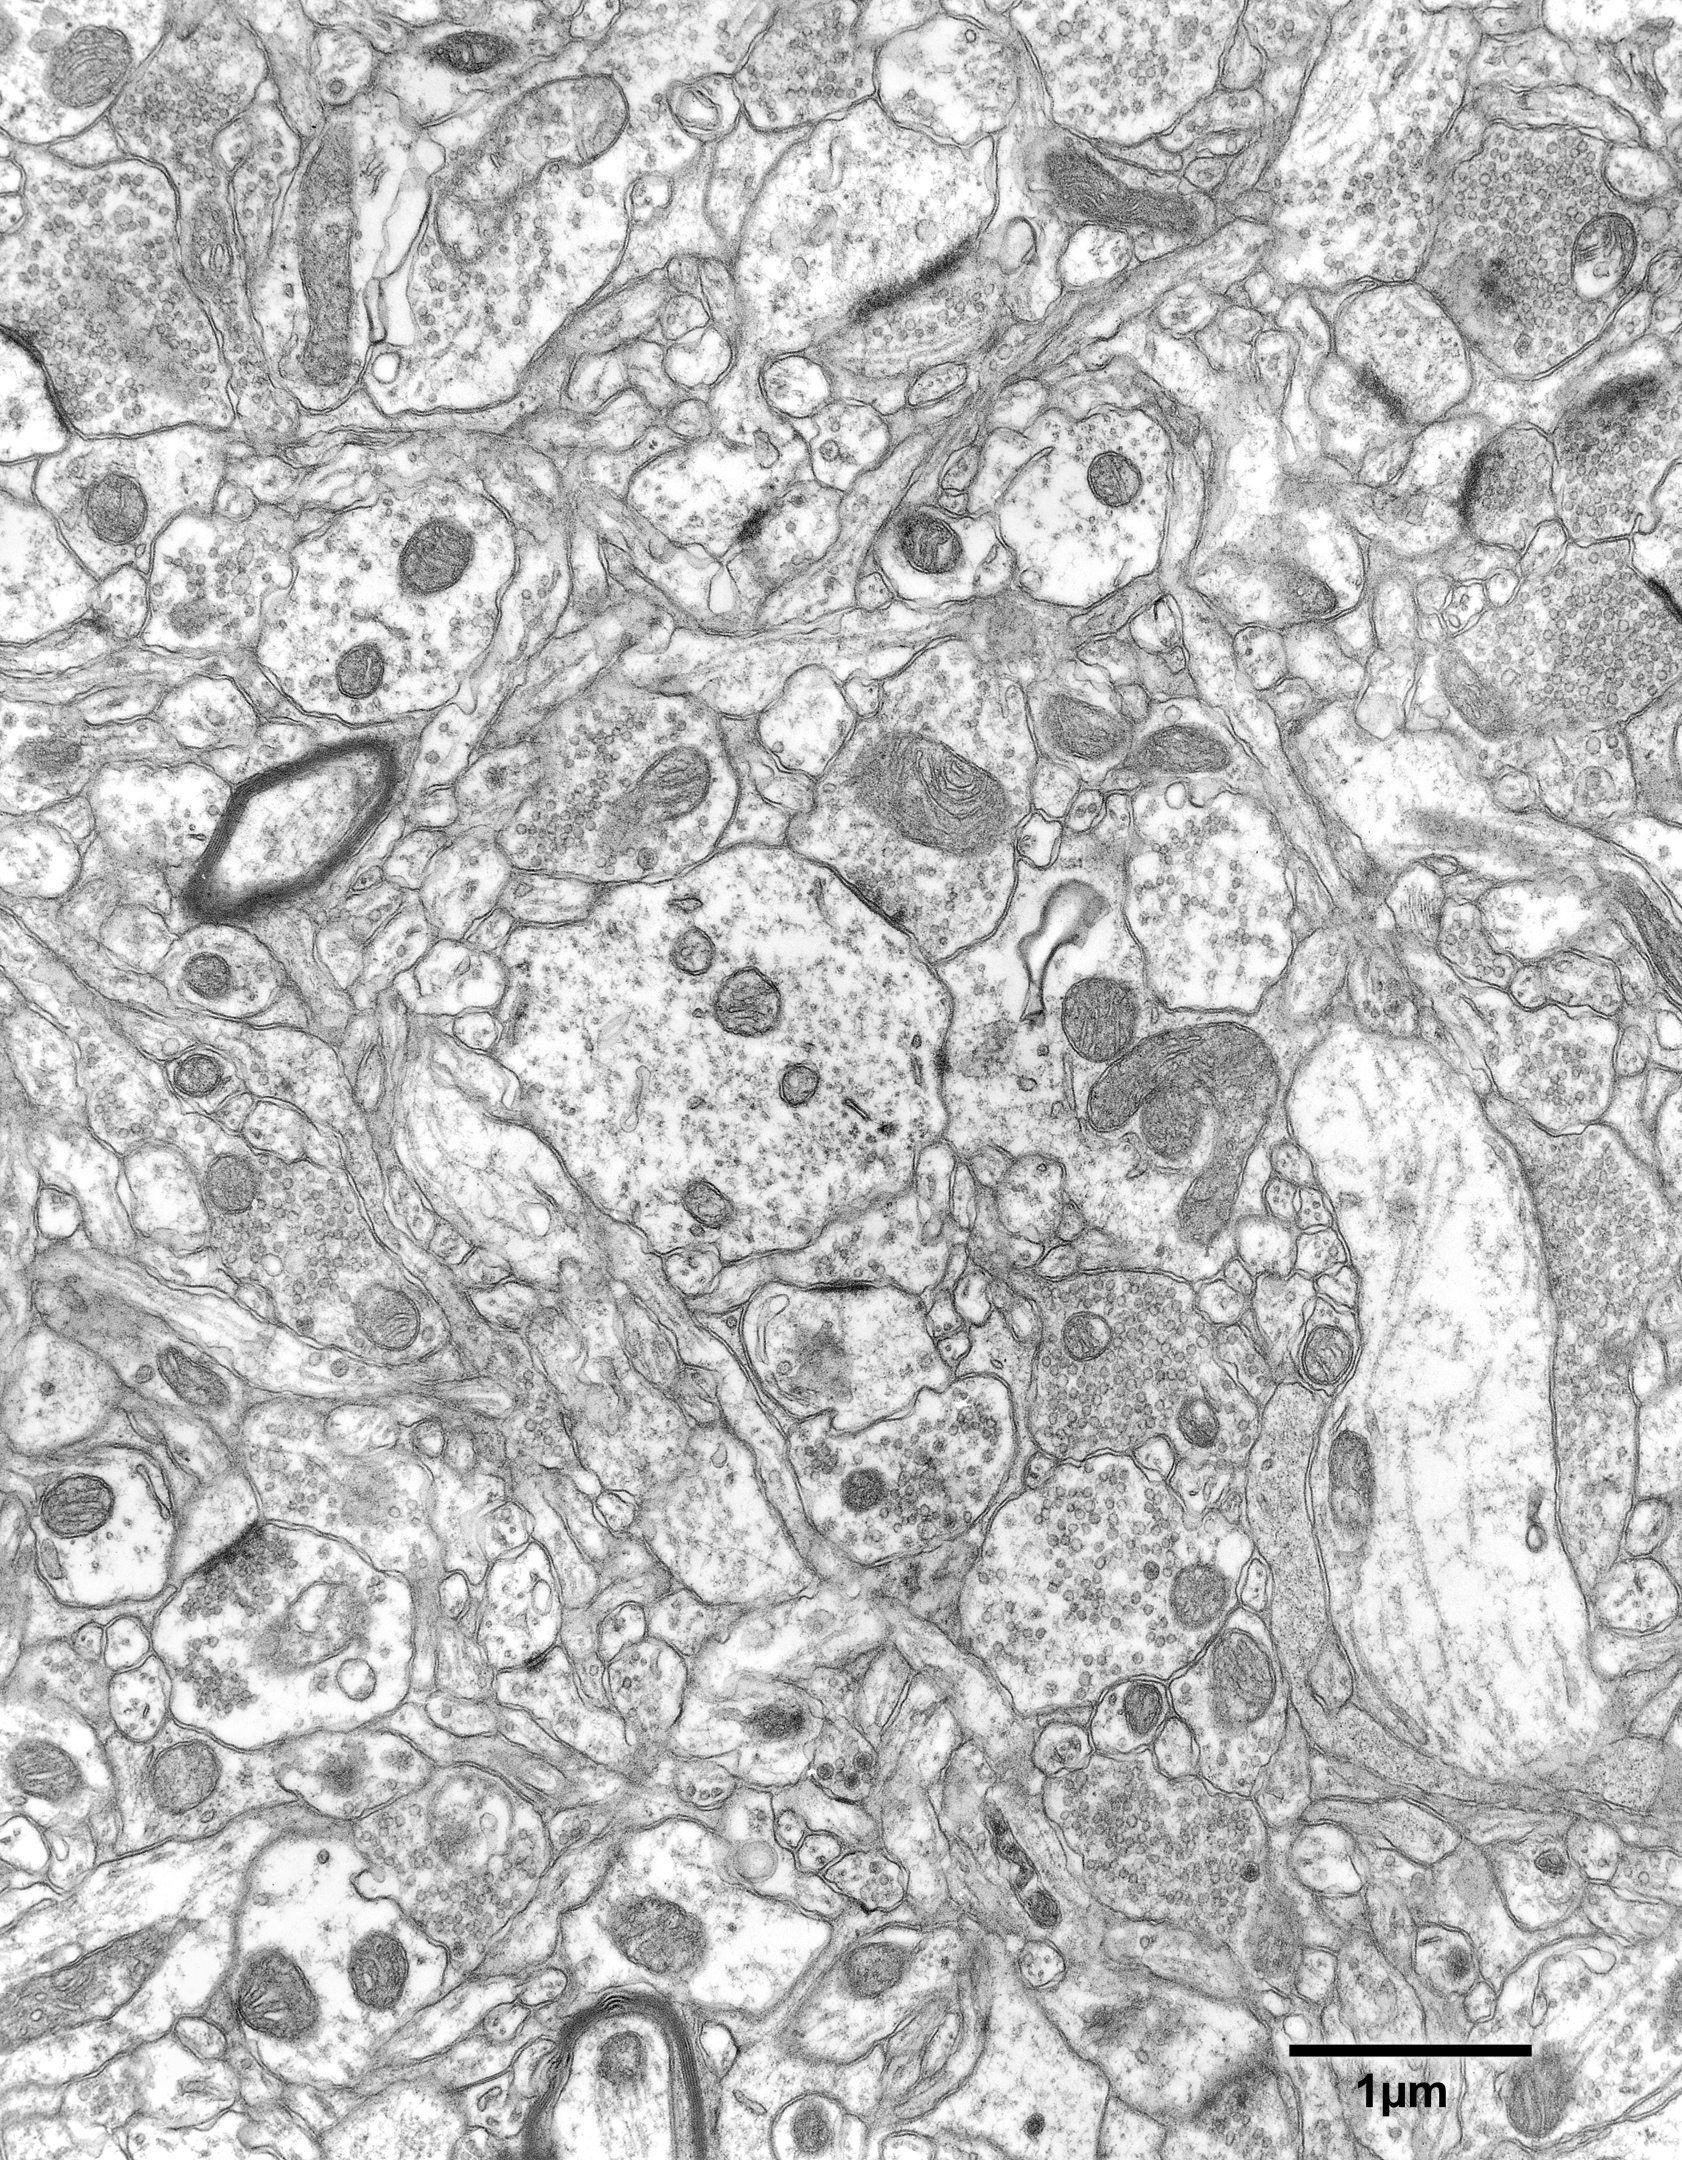

Figure 9.2

Fig. 9.2. Neuropil in layer 5 of area 46 of a 25 year old monkey.